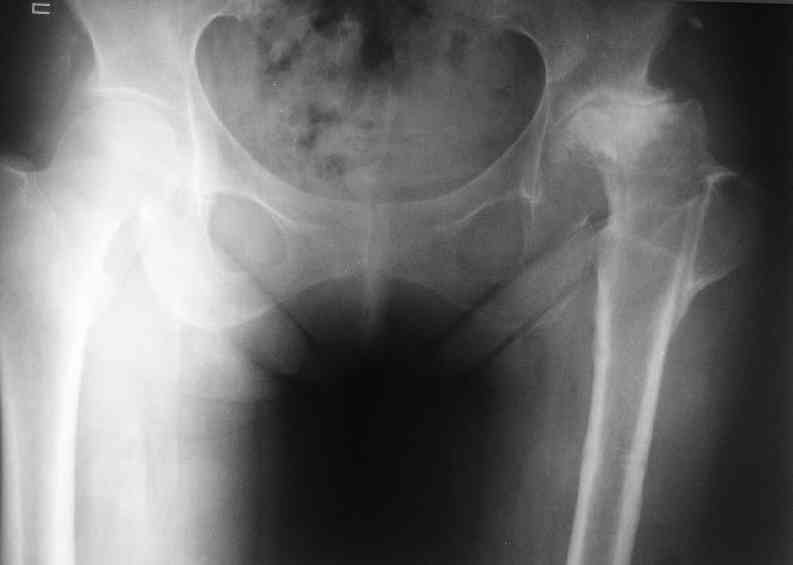

Не такое уж страшное укорочение по снимкам.Вчера прооперирован похожий случай.Обошлись без релиза и аппаратного низведения. укорочение было 4 сантиметра.Теперь ножки ровные.